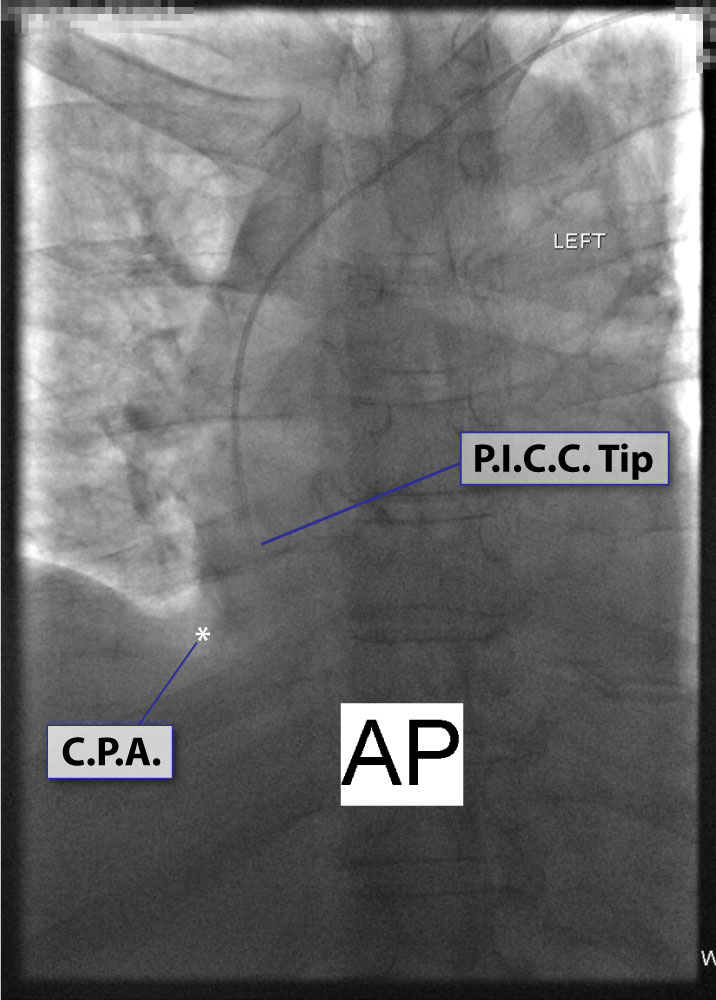

2. On inspiration upright CXR, the tip of VAD is ideally at C.A.J. See Fig.# 09 - Gallery.

3. Chest x-ray rotation tissues: Not infrequently, the chest x-ray will be rotated causing the right cardiac margin to deviate from its normal AP appearance. In such situations, depending on the degree of rotation, an estimation of the SWEET SPOT™ is all that may be possible. In such circumstances, the right cardiophrenic angle is the most reliable anatomic landmark. Since the right atrium is immediately cephalad to a normally positioned right cardiophrenic angle, a reliable estimation of acceptable catheter tip location is still possible. The height, and consequently the width of the rectangular Sweet Spot™ box will be less exact and therefore a relatively short catheter tip position may require a non- rotated chest x-ray to confirm an acceptable location. Aim for the right atrium. See Figs. T.1, T.2, and T.3.

17. “A good use of carinal landmarks for catheter tip location- right sided White Out.” See Fig. T.4 - Carina.